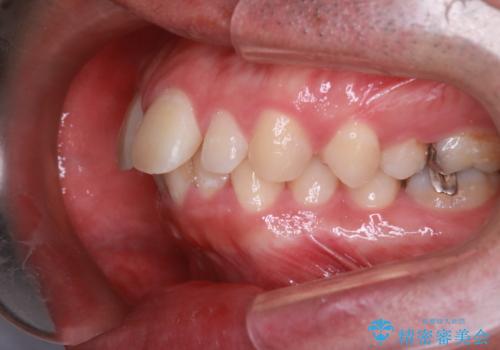

インビザラインにて治療を行いきれいな歯並びをつくることができました。

奥歯の噛み合わせもきちんと仕上げることができました。